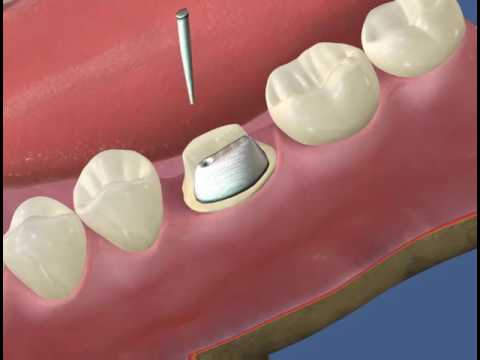

Циркониевые коронки и штифты: современные решения в стоматологии

Раздел: Необычные решения